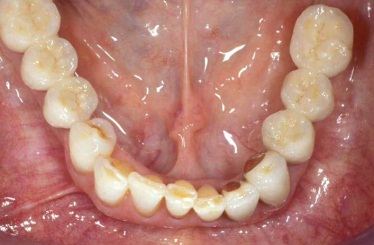

Během let může postupnou ztrátou zubů zůstat v ústech omezený počet zubů, které umožňují držení zubních náhrad.

V důsledku přetížení zbylých zubů např. houpavými pohyb snímacích náhrad dochází k uvolnění těchto zubů a držení můstků a protéz je tak velmi těžké. V těchto případech můžeme pomocí implantátů zvýšit počet pilířů a tím zabránit přetěžování a ztrátě zbylých zubů